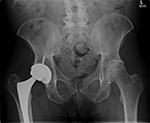

Metal-on-metal left hip arthroplasty with metallosis and bony erosions |

68 year-old woman with left hip metal-on-metal prosthesis. Bony erosions (arrows) are evident on the greater and lesser trochanters from probable metallosis with pseudotumor formation. |